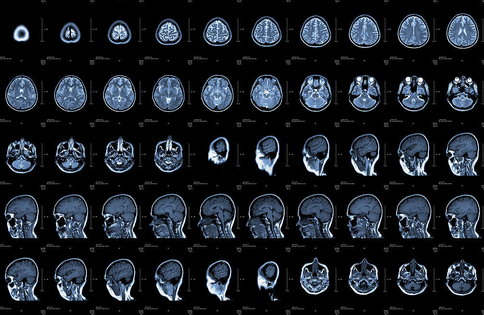

X光、CT、B超、核磁共振……这些都是医疗中常用的影像学检查法,但是它们有什么区别,看什么病应该照什么影像呢?